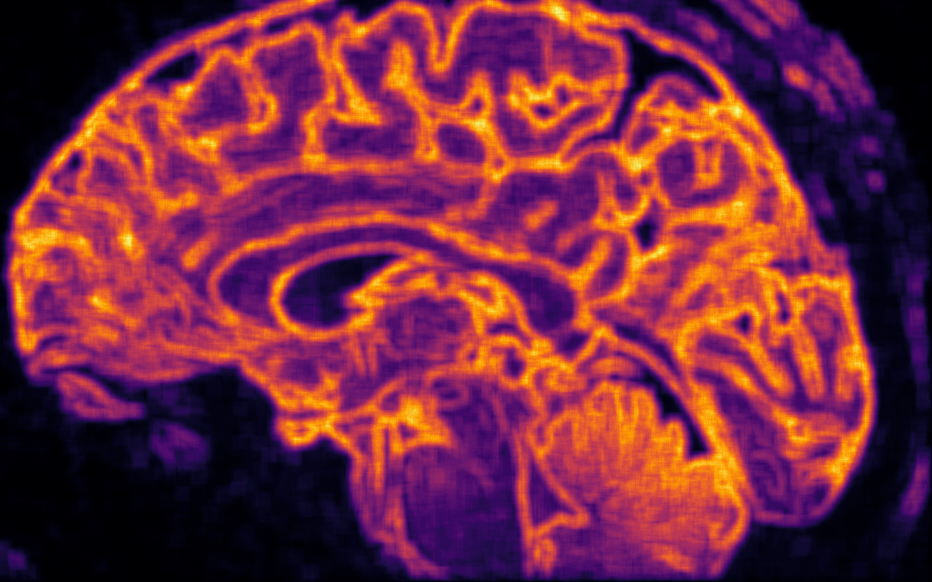

Voir n’est plus regarder : c’est comprendre la structure du monde cellulaire.

Loin du contraste classique, ϕ explore la richesse interne des tissus.

Elle distingue l’homogène du structuré, le bruit du sens, et redonne au regard médical une dimension topologique : celle de l’information vivante.

Les structures fines, souvent invisibles à l’œil nu, s’y dessinent comme des reliefs entropiques — un paysage du corps, révélé par la mathématique du vivant.